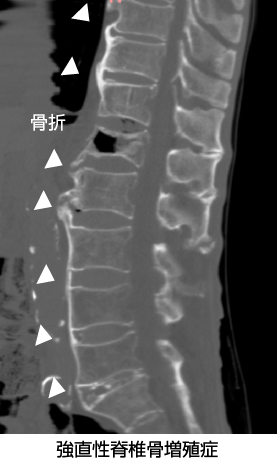

強直性脊椎骨増殖症を合併した椎体骨折

骨折部周囲に骨性架橋をみとめた場合は、骨折部に応力が集中するため注意を要する。